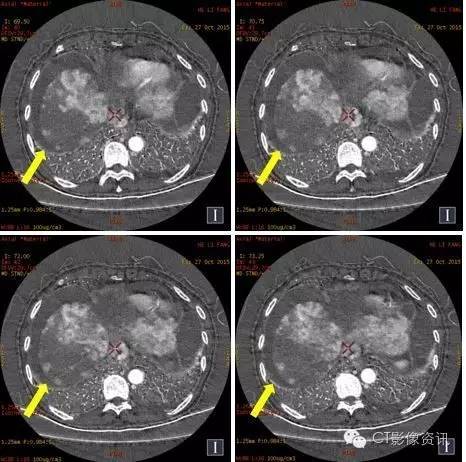

门静脉癌栓的显示

常规图像69keV

60keV

碘基图像

门静脉显示在60keV对比度更高,碘基图对含碘的结构显示非常敏感。